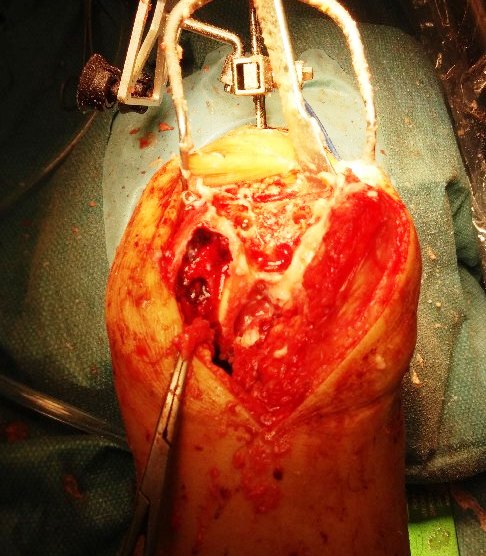

A standand midline incision and medial parapatellar approach was used. The osteoarthritis was confirmed to be mainly affecting the medial and patellofemoral compartments of his left knee.

Registration of the knee were done and the Makoplasty RIO robotic arm was prepared.

Burring of the bone were completed using the RIO robotic arm.

Trial implants showed good positioning of the implants.